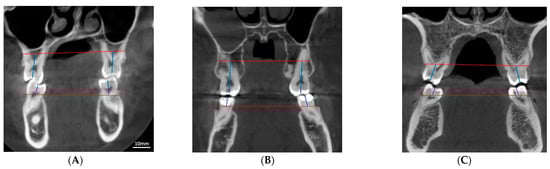

2. Materials and Methods